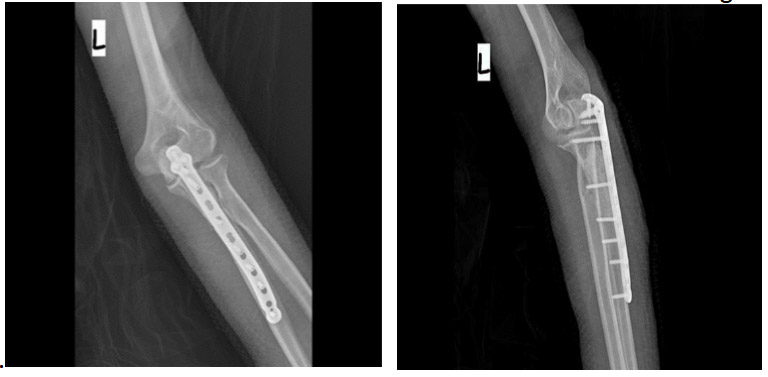

During the operation: The procedure involves tumor removal, fixation with a titanium plate, and reinforcement of the resulting cavity with bone cement.

Post-surgery: The X-ray shows that after removing the tumor from the bone, the resulting cavity is filled with bone cement and reinforced with an anatomical titanium plate.